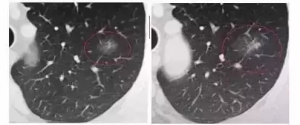

日本体检复查过程中结节出现体积增大,或磨玻璃中间出现实性成分或原有实性成分增多时,提示可能是恶性结节,要及时手术切除。

下图是大小未变,实性成分增多

一年前 一年后